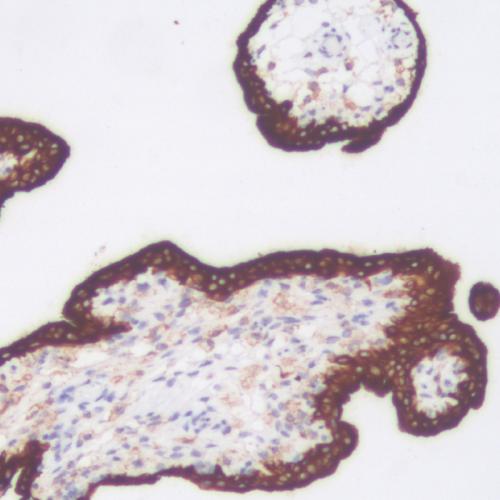

• CD34

CD34

CD34抗體試劑(免疫組織化學(xué)) 閩廈械備20180070號(hào)